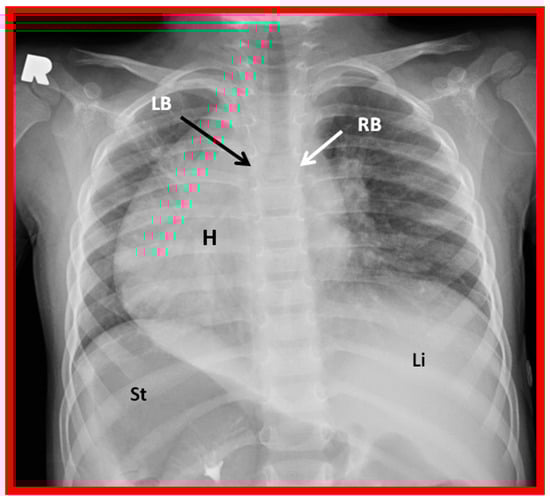

5.2.3. Tracheobronchial Tree Pattern

In typical patients with situs solitus, the bronchus on the right side is short and wide and descends somewhat steeply, whereas the bronchus on the left side is longer and narrower than the right bronchus and descends rather horizontally (Figure 22A and Figure 23). On the contrary, in patients with situs inversus, the tracheobronchial tree configuration is inverted (Figure 22B and Figure 24) [2,3,4,5]. The tracheobronchial tree pattern seems more correct than the above two approaches to identifying the atrial situs [2,26,27]. Tomography has been used in the past [27] to more accurately determine bronchial morphology and measure the bronchial lengths but is not routinely used at the present time because of increased radiation exposure associated with tomography and the availability of other imaging studies.

Figure 23. A chest roentgenogram of a patient with situs solitus demonstrating a wide and short right bronchus (RB) which descends somewhat steeply, whereas the left-sided bronchus (LB) is narrow and long and traverses horizontally. The liver (Li) is seen on the right side, and the stomach (St) bubble is seen on the left side, consistent with situs solitus. Mild cardiac enlargement and increased lung vascular patterns are also seen. UAC indicates an umbilical arterial catheter, and UVC points to the catheter in the umbilical vein. Modified from reference [4].